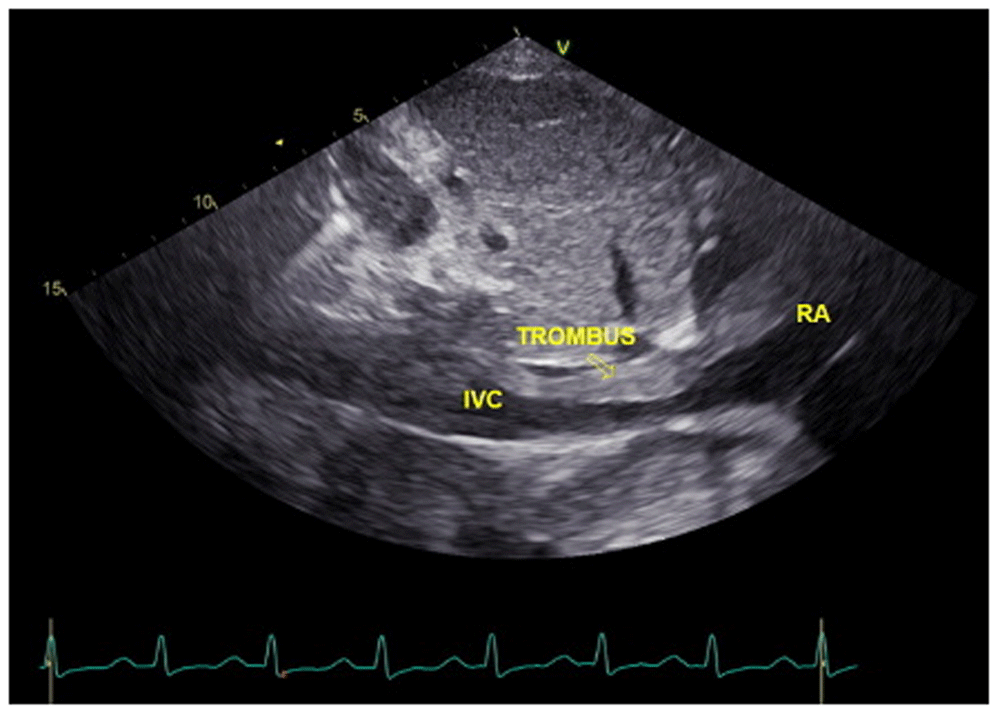

In laboratory findings, serum electrolytes revealed hypokalemia (K: 3.3 mmol/L; normal range 3.5–5.1 mmol/L), serum protein showed hypoalbuminemia (albumin: 3.1g/dL; normal range 3.4–5.0 g/dL), while other parameters were between normal limits. An electrocardiogram (ECG) showed sinus tachycardia rhythm 125 bpm, right-sided frontal axis, horizontal axis clockwise rotation, and slow progression of R waves at V1–V4 (Figure 1). A chest X-ray showed cardiomegaly, pulmonary congestion, and minimal bilateral pleural effusion (Figure 2). Echocardiographic examination revealed moderate mitral regurgitation (dilated mitral annulus), dilatation of all cardiac chambers (LVIDd 5.8 cm), visible thrombus in IVC to RA, decreased left and right ventricular systolic function (EF teich 35%, TAPSE 1.3 cm), and global hypokinetic of the left ventricle with eccentric LVH. The scans from a transthoracic echocardiogram (TTE) showing thrombus is shown in Figure 3 and Figure 4.

A chest CT scan (Figure 5) showed right pulmonary artery embolism at ± 5.9 cm from bifurcation on the anterior side of the intermediate right bronchus; emboli on the left pulmonary artery bifurcation and the left pulmonary artery basal part; multiple right intraatrial hypodense lesions not showing contrast enhancement leading to a visualization of the right intraatrial thrombus; pulmonary infarction in the lateral-posterior segment of the base of the inferior lobe of the right lung, the lateral-posterior segment of the base of the inferior lobe of the left lung, and the anterior segment of the superior lobe of the left lung; and superior vena cava thrombus at VTH level 1-5. Figure 6 shows the protruded thrombus in the right atrium passing through the tricuspid valve. TTE also showed the position of the thrombus moving from the inferior vena ca va towards the right atrium (Figure 7). The movement of the large protruding thrombus can be seen in supplementary video files 1–35–7.